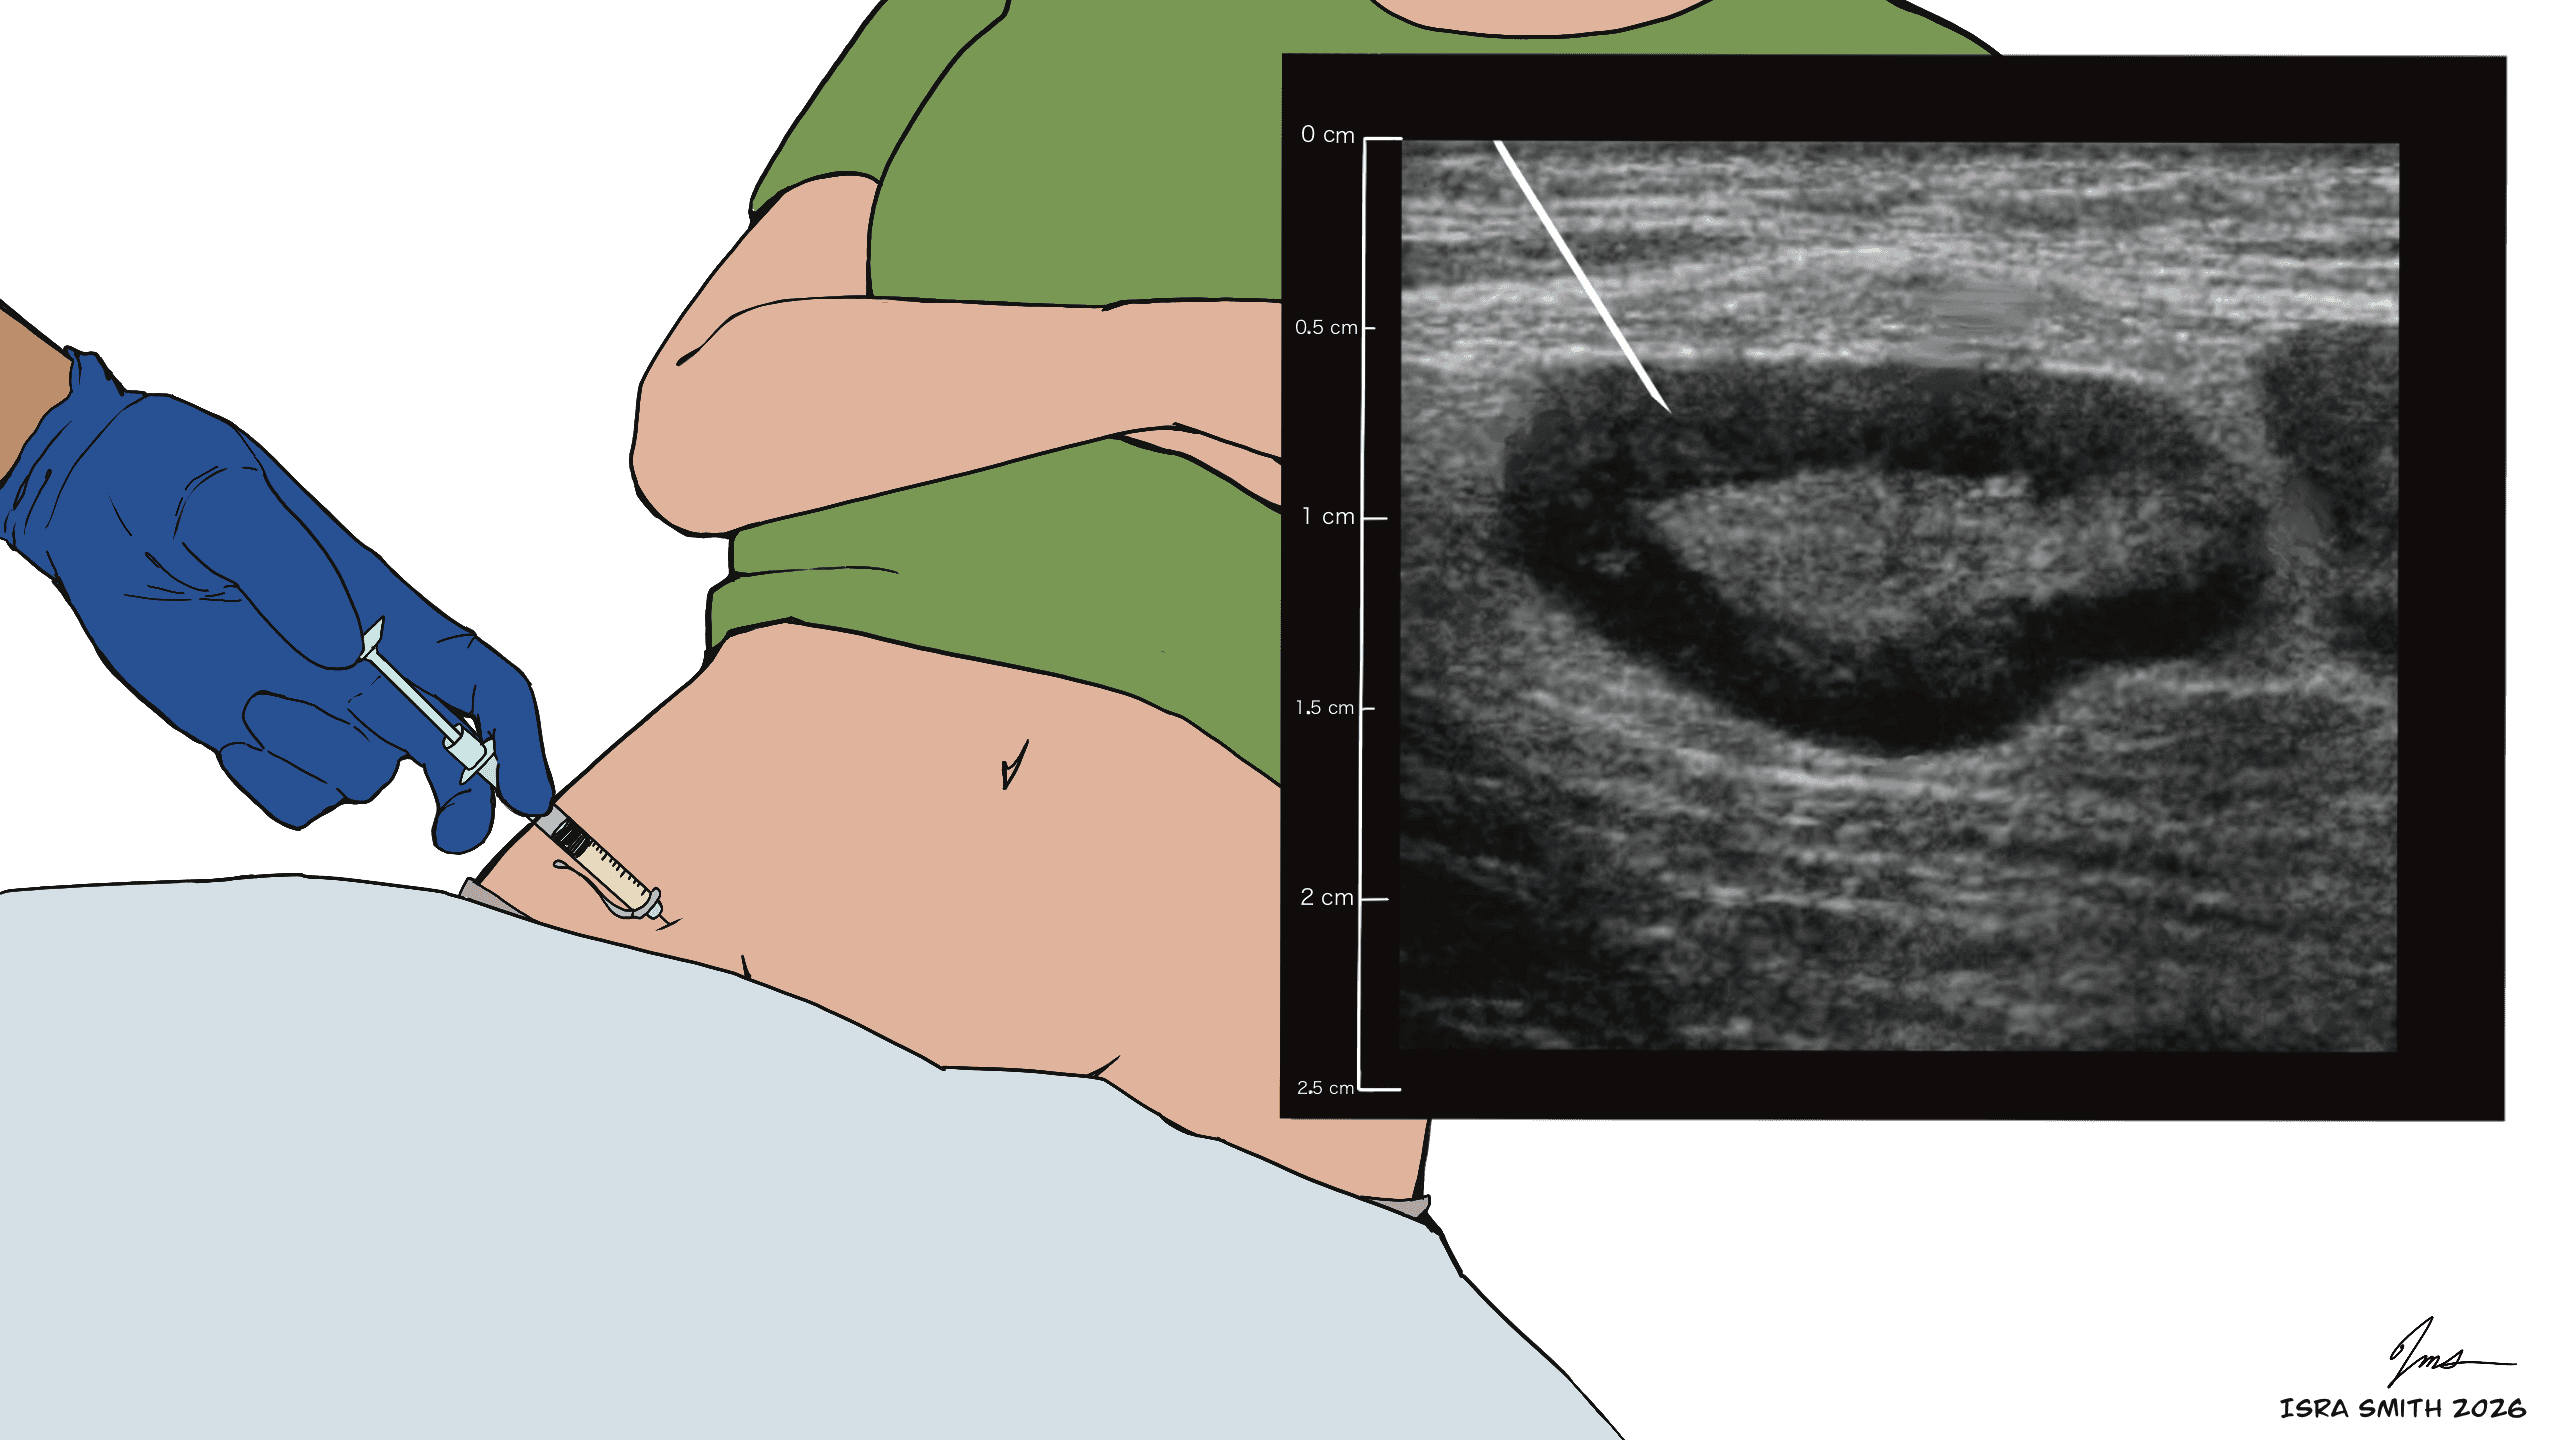

These images illustrate how ultrasound is used during ILIT to locate superficial lymph nodes and guide accurate allergen delivery during treatment.

Yes. ILIT uses low doses of allergen extract, and real-time ultrasound guidance ensures precise placement inside the lymph node. Most patients experience only mild, temporary soreness at the injection site.